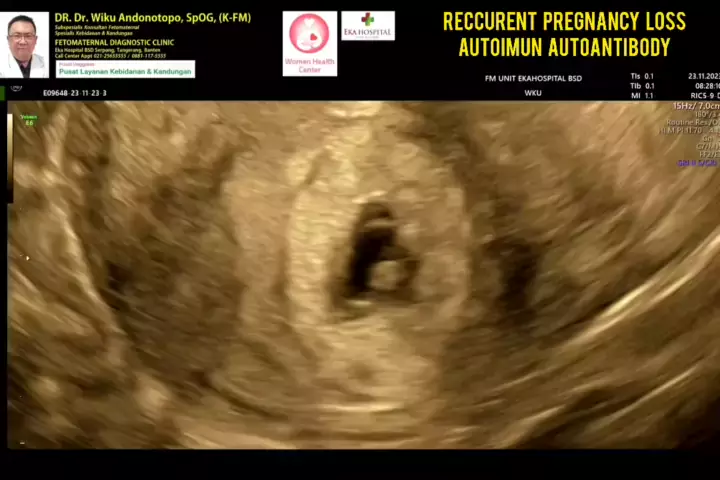

Recurrent Pregnancy Loss..... #skriningkehamilan #drwikuandonotopo #drwiku_andonotopo #polikandunganekahospitalbsd #ekahospitalbsd #ekahospitalcibubur #ekahospitalpekanbaru #ekahospitalbekasi #rsiafamilypluit #grandfamilypik #usgkehamilansehat #usgkehamilan #usg4d #usg4dimensi #fetomaternal #usgfetomaternal #konsultanfetomaternal #fetomaternalpontianak #fetomaternalekahospitalbsd #fetomaternaljakarta #fetomaternalserpong #fetomaternaltangerang #fetomaternalmedan #fetomaternalpalembang #fetomate...